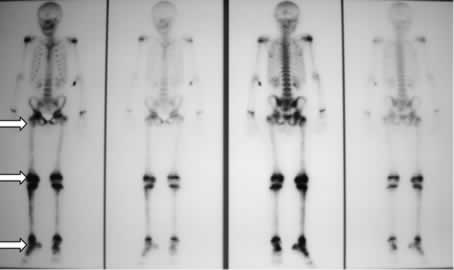

Quello che colpiva nella valutazione della diagnostica per immagini era l'aspetto, in corso di scintigrafia, di ipercaptazione di tutto il femore , non solo delle articolazioni, dato che peraltro, vista l'evidenza di artrite concomitante, non era stato particolarmente valorizzato pensando ad una generica �ipersensibilit�� della scintigrafia. (figura 1)

Figura 1: riscontro di zone multiple di captazione (ginocchio, articolazione tibio-tarsica, femore destro e coxo-femorale destra).